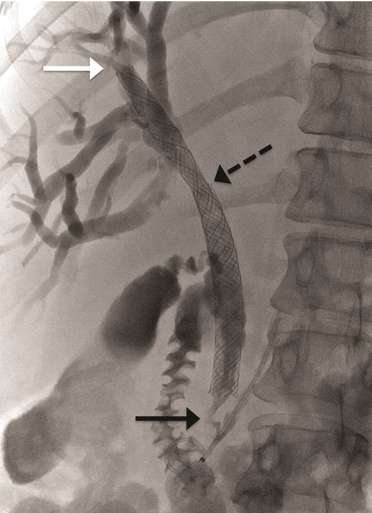

A 52-year-old female presented to her general physician with a four-month history of right upper quadrant discomfort and was referred for an outpatient abdominal ultrasound scan. This revealed intrahepatic duct dilatation and subsequent computed tomography (CT) scan of liver and magnetic resonance cholangiopancreatography (MRCP) confirmed imaging features of a 24-mm intrahepatic cholangiocarcinoma. This was located immediately proximal to the confluence of the left and right hepatic ducts and was causing obstruction of the left intrahepatic ducts. There were no distant metastases identified on imaging or staging laparoscopy. Endoscopic retrograde cholangiopancreatography (ERCP) and direct endoscopy of the bile duct was performed with the aim of directly visualizing the tumor to obtain a biopsy and confirm the diagnosis. Cannulation of the bile duct was difficult and a pre-cut sphincterotomy was performed in an attempt to facilitate access, but this was unsuccessful. The procedure was complicated by a duodenal perforation with retroperitoneal collection and pancreatitis, which delayed definitive management. The tumor was thought to be resectable after initial imaging, but unfortunately, repeat CT scan demonstrated progression over the subsequent weeks with involvement of the right portal vein and right intrahepatic ductal system. The patient was discharged two weeks after the ERCP, but re-presented to the emergency department a week later complaining of abdominal pain and nausea. At this time, she was noted to be clinically jaundiced. Fluoroscopically guided percutaneous trans-hepatic cholangiography (PTC) and bare metal stent insertion was therefore performed under conscious sedation as a palliative procedure to relieve the obstruction. Following puncture of the right anterior ducts with an introducer set ('Accustick' introducer set, Boston scientific®), complete occlusion of the ductal system was demonstrated. There was no cross filling of the left segmental ducts. The obstruction was traversed with a guide wire. A 10x70 mm USEMS (Placehit Biliary WALLSTENT, Boston Scientific®) was then deployed across the stricture and was positioned with 3 cm of stent proximal to the tumor to allow maximum proximal expansion within the duct and ensure optimal flow of bile from the intrahepatic ducts (Figure 1). Free flow of contrast into the common bile duct was demonstrated, indicating successful procedure and no balloon expansion was required. The day after the procedure, the patient complained of abdominal pain and nausea, and developed a temperature of 38.5°C. She was noted to be more jaundiced. Serum bilirubin rose from 84 mmol/L (normal range: 21–100 mmol/L) before the stent placement to 268 mmol/L two days post-procedure. Full blood count revealed elevated white cell count of 21x109/L (normal range: 4–11x109/L) and serum C-reactive protein (CRP) increased to 47 mg/L (normal range: 4–8 mg/L). A diagnosis of biliary sepsis was made. Blood cultures grew Enterococcus faecium with resistance to amoxicillin. Teicoplanin, gentamycin and metronidazole were commenced. The liver function tests failed to improve over the next few days, and a repeat PTC was performed eight days after the first procedure which demonstrated that the stent had slipped through the stricture into the extra-hepatic biliary tree, and that the right intrahepatic duct was once again completely occluded (Figure 2). A wire was placed across the occlusion and through the centre of the migrated stent, and a further uncovered 10x70 mm self-expandable metal stent (Placehit Biliary WALLSTENT, Boston Scientific®) was then placed across the stricture and deployed, the distal end of the new stent sited within the proximal end of the migrated one. There was some wasting in the region of the tumor which was dilated using a balloon dilatation catheter (35LP Low-Profile PTA Balloon Dilatation Catheter (0.35", 8 mm diameter 4 cm length). There was subsequent free flow of contrast into the duodenum indicating a successful procedure (Figure 3). Following the placement of the second stent, the patient improved with reduction in pain and nausea. Serum bilirubin dropped from 195 mml/L to 119 mmol/L within two days, and she was discharged four days later for outpatient oncology follow-up. |